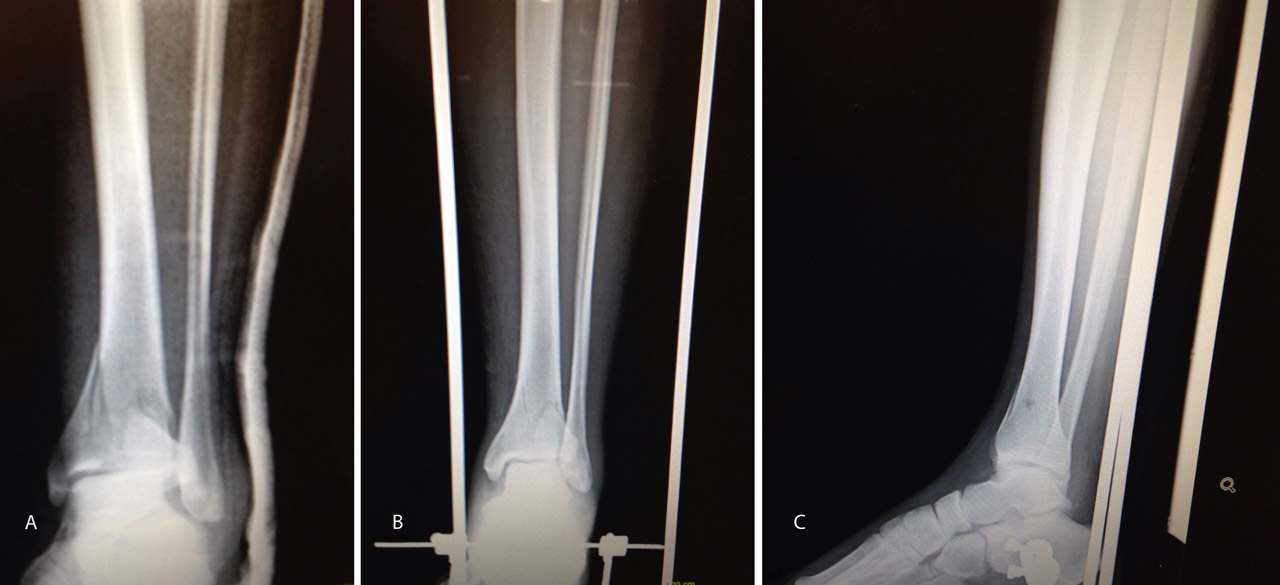

Figura 17. Caso 3: fractura tipo C. Radiografías sin tracción y con tracción comprobando la reducción.

En este caso, es esencial observar las Rx con y sin tracción que nos indican cómo se va a comportar la fractura. Si la fractura es reductible en tracción, es muy probable que podamos realizar una osteosíntesis con restitución completa de la superficie articular. Al realizar la TC, apreciamos la disposición de los fragmentos para marcar una estrategia de reducción bajo control radioscópico y artroscópico, y colocación de los tornillos canulados que fijarán la epífisis distal de la tibia.